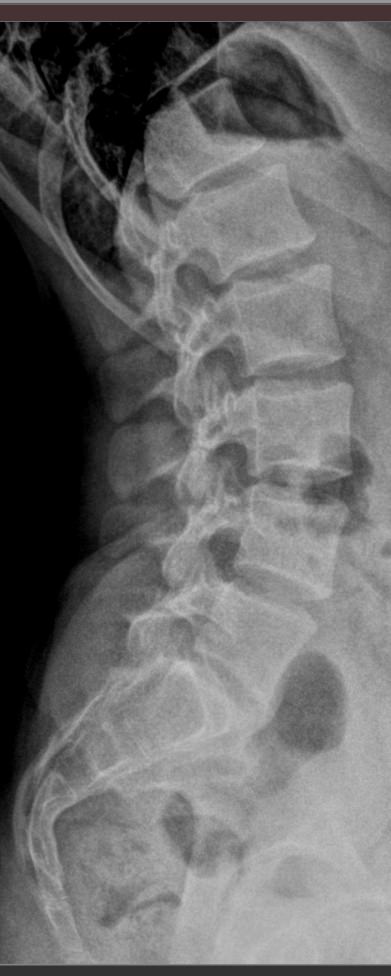

В исследование входит 3 снимка, показывающих состояние поясничного отдела в разных положениях. Однако бояться чрезмерного облучения не стоит: цифровые модели рентгеновского оборудования последнего поколения излучают минимально необходимую для четкого снимка дозу. После данного исследования количество облучения, полученного организмом, будет составлять едва ли десятую часть от допустимой годовой дозы.

На первом снимке будет видно, сохранен ли естественный поясничный лордоз или есть его изменения. На тестовых снимках будут видны:

• Изменение высоты межпозвонковых дисков при отсутствии патологий;

• Неизменность межпозвонковых пространств при наличии функционального блока;

• Смещение позвонков вперед или назад (вправо или влево) при их патологической подвижности;

• Деформация передней стенки позвоночного канала, когда подвижный позвонок смещен кпереди или кзади (вправо, влево).

Также будут видны остеофиты, опухоли, аномалии развития.

Процедура выполняется без подготовки. Пациент раздевается до белья, надевает защитный фартук и встает к пластине детектора. Чаще всего нужно определить смещение в передне-заднем направлении, поэтому пациент встает боком и поднимает руки за голову или держится ими за стул. Выполняется 3 снимка:

• В привычном  положении, то есть обычный боковой;

• В условиях максимального разгибания назад;

• В условиях сгибания вперед.

Реже требуются пробы для определения бокового смещения позвонков. Вы встаете к пластине спиной и, после снимка в прямой проекции, поочередно наклоняетесь вправо и влево. В запущенных случаях при сильной боли и невозможности выполнять пробы стоя, их делают сидя или лежа. Рентгенолаборант поможет вам правильно встать или лечь и безопасно наклониться. Каждый снимок длится около 1 секунды, во время съемки нельзя двигаться, но можно дышать.